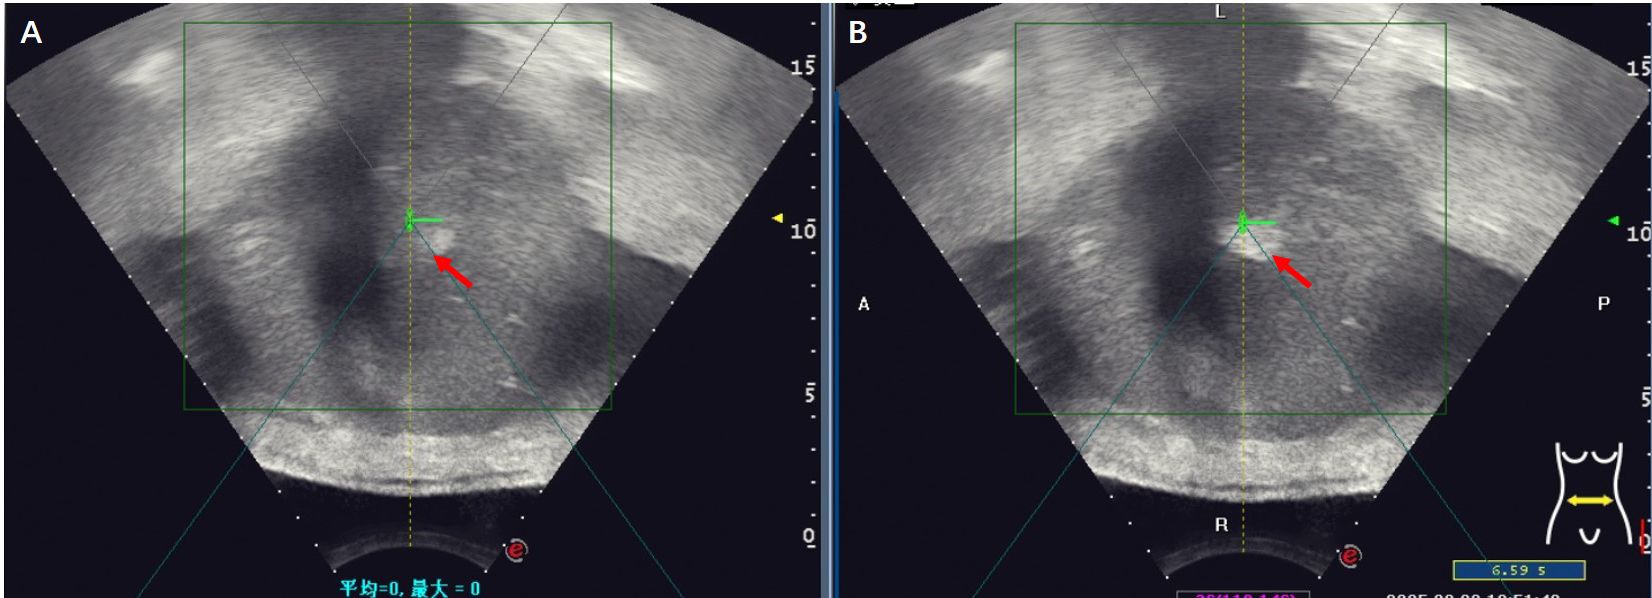

Efficacy and Safety of High-Intensity Focused Ultrasound Ablation Under General Anesthesia in Older Hepatocellular Carcinoma Patients

Background: Older patients often have comorbidities, leading to a higher risk of delayed recovery while under general anesthesia. High-intensity focused ultrasound (HIFU) for patients with hepatocellular carcinoma (HCC) usually requires general anesthesia to alleviate procedure-related pain and ensure immobilization. This study aimed to evaluate the safety and efficacy of HIFU for the treatment of older patients with HCC, and to explore the associated prognosis and risk factors. Methods: A total of 174 patients with HCC who underwent HIFU were enrolled in this study and divided into three age groups: <60 years (n=100), 60–74 years (n=55), and ≥75 years (n=19). The risks of general anesthesia associated with HIFU were observed, and the ablation effects of HIFU were evaluated using contrast-enhanced CT or MRI. Survival analysis, prognosis and risk factors were analyzed. Results: The prevalence of comorbidities was 73.68%, 52.72%, and 26.00% in patients aged ≥75 years, 60–74 years, and <60 years, respectively. The difference between the three groups was significant (P < 0.001). The rates of complete response (CR), partial response (PR), and ORR were 25.61%, 46.34%, and 71.95% in patients aged <60 years, 34.04%, 40.42%, and 74.46% in patients aged 60–74 years, and 12.50%, 62.50%, and 75.00% in patients aged ≥75 years, respectively. 1-year and 2-year overall survival (OS) rates in patients aged <60, 60–74, and ≥75 years were 78.4% and 70.5%, 84.5% and 75.3%, and 72.4% and 43.4%, respectively. There were no significant differences in ORR and OS between the three groups (P = 0.937 and 0.055, respectively). No significant difference of the median interval time of anesthesia recovery between three groups occurred (P = 0.208) and no other anesthesia-related complications were observed. CNLC stage Ⅲ was an independent prognostic factor (P = 0.049). AFP ≥20 ng/mL was an independent risk factor (P = 0.016), whereas the combination of other local treatment methods was a protective factor (P = 0.016). Conclusions: HIFU ablation under general anesthesia for older HCC patients is safe, feasible and effective